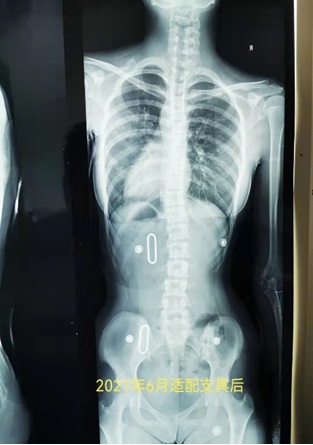

13岁患者2021.6初诊,L1向右侧弯cobb23°,身体中线向右侧偏移严重,适配支具后减至10°以内,身体回归中线。